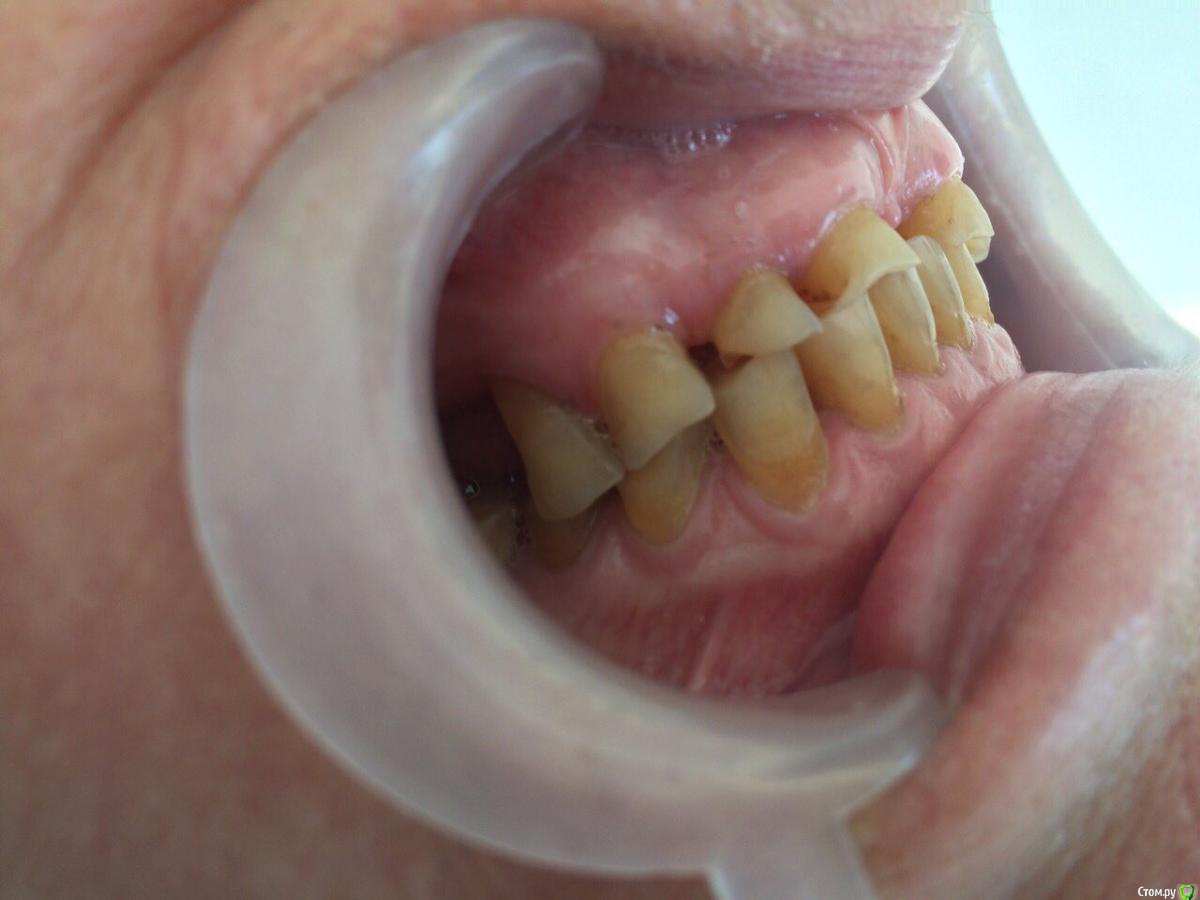

dr.Dre Опубликовано 31 июля, 2017 Поделиться Опубликовано 31 июля, 2017 Добрый вечер уважаемые коллеги ,пациентка 70 лет хочет металлокерамику,каналы очень склероризированые,как правильно протезировать при таком прикусе? Ссылка на комментарий

chervoncevdaniil Опубликовано 1 августа, 2017 Поделиться Опубликовано 1 августа, 2017 (изменено) пока пациентка хочет вверхИ что,вы хотите под такую анатомию нижних зубов ей сделать новый верх?Если хочет постоянные только верх,то на низ времянки на боковые,фронт хотя бы композитом подкорректировать,а дальше пусть хоть по зубу нижние в постоянные переводит,иначе ерунда,а не работа получится Изменено 1 августа, 2017 пользователем chervoncevdaniil 2 Ссылка на комментарий

bakagaidzin Опубликовано 1 августа, 2017 Поделиться Опубликовано 1 августа, 2017 (изменено) По уму надо делать все сразу,снять лицевую,определить ЦС,посчитать LVI и передать эти данные технику для ваксапа.а дальше уже в идеале конечно сделать мокап длительного,потом менять его на постоянные коронки..Но это все в идеале,сомневаюсь что на практике Вы это осуществите у 70 летней пациентки...плюс тут диастема огромная,нужна ортодонтия Изменено 1 августа, 2017 пользователем bakagaidzin 3 Ссылка на комментарий

Bobby Опубликовано 7 августа, 2017 Поделиться Опубликовано 7 августа, 2017 В данном случае, как правильно подметили, невозможно сделать один зубной ряд, не проводя реконструкцию антагонистов. Ссылка на комментарий